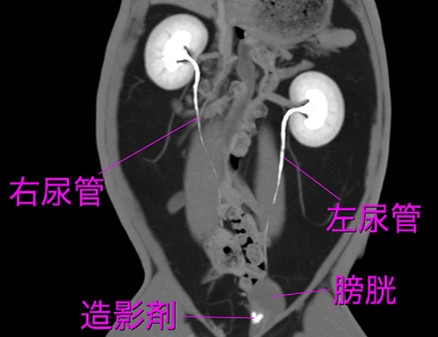

CT検査

CTでは腎臓のサイズを測定し、腫大や萎縮を評価できます。また、腎辺縁の不整や石灰化なども詳細に評価可能です 。CTはX線検査よりも高感度に石灰化を検出できる特徴があります 。初期の腎嚢胞、水腎症、腎盂の蓄膿も評価対象となります 。造影剤(ヨード製剤)を静脈内投与して行う造影CT検査は、腎臓の血流(灌流)と排泄機能の評価に用いられます。健康な腎臓では、造影剤投与後にまず皮質が強く濃染され(皮質期)、次いで髄質が濃染され(髄質期)、その後造影剤が腎盂へ排泄されます(排泄期) 。間質性腎炎や糸球体腎炎など、腎実質自体に障害がある場合、腎臓への血流や機能の低下により、この造影効果が全体的または部分的に低下します。実質が正常ほど濃染されない、または濃染までに時間がかかるといった所見が見られます。腎実質が斑状(まだら)に不均一に造影される場合は、線維化や炎症が不均一に存在することを示唆します 。造影CT検査は、腎梗塞の診断において非常に重要です 。急性期(発症から数日以内)の腎梗塞では、造影剤投与後の「動脈相」や「腎実質相」において、血流が途絶えた領域が特徴的な楔状の造影欠損域として描出されます。